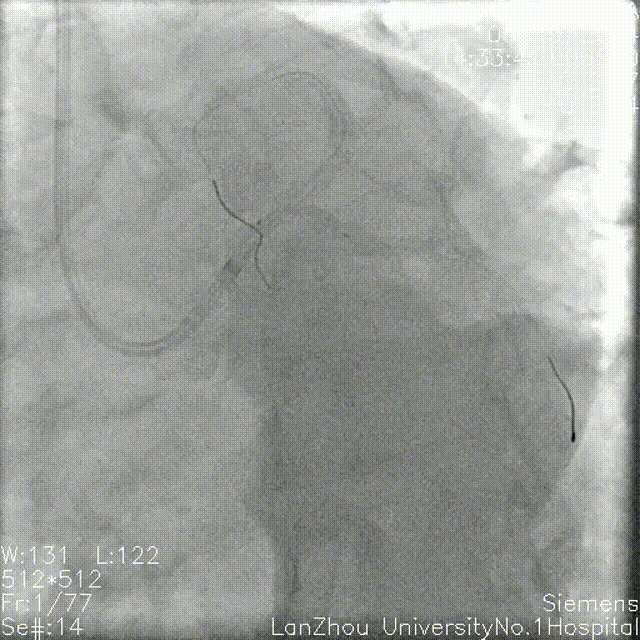

头位造影:

LM较短,末端可见重度狭窄,前降支近中段全程弥漫性狭窄伴钙化;

回旋支次全闭,可见钙化影。

右肩造影:

前降支近中段全程弥漫性狭窄伴环形钙化,最重处95%狭窄;

对角支开口狭窄不重,角度不大,可能不需要导丝保护。